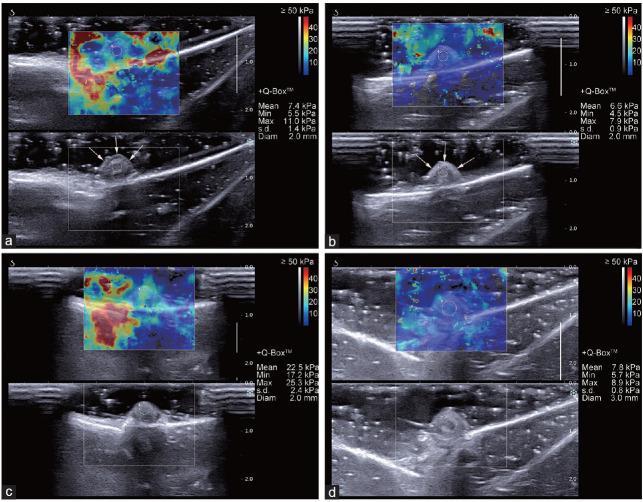

This study explored the usefulness of two-dimensional shear wave elastography (2D-SWE) in the early assessment of corpora cavernosa fibrosis (CCF). New Zealand male rabbits were randomly assigned to an experimental group or a control group. Recombinant human transforming growth factor beta 1 (TGF-β1) was injected into the dorsal penis tissue of rabbits in the experimental group. Conventional ultrasound and 2D-SWE examinations were performed before and 20 days after injection. Penile histological analysis was performed by hematoxylin-eosin staining, sirius red staining, and immunohistochemistry. Measurement of 2D-SWE examination results was performed using shear wave elastography quantitative measurement (SWQ). Histological analysis outcomes were the proportion of smooth muscle cells (SMCs), collagen fibers (CFs), collagen type I (Col I), and collagen type III (Col III), as well as the SMCs/CFs ratio, measured by sirius red staining. Other histological analysis outcomes were the positive area proportion (PAP) of TGF-β1 (PAP), fibronectin (PAP), and Col III (PAP), measured by immunohistochemistry. After recombinant human TGF-β1 injection, SWQ was higher in the experimental group than that in the control group (P < 0.001); however, there were no differences in conventional ultrasound results. There were significant differences in histological outcomes between the two groups (all P < 0.05). These results indicated that 2D-SWE was superior for identifying early histological changes in CCF.

本研究探讨了二维剪切波弹性成像(2D-SWE)在评估阴茎海绵体纤维化(CCF)早期病变中的作用。新西兰雄性兔随机分为实验组和对照组。实验组兔阴茎背部组织注射重组人转化生长因子β1(TGF-β1)。注射前及注射后 20 天分别行常规超声及 2D-SWE 检查,行苏木精-伊红(HE)染色、天狼星红染色和免疫组织化学染色行阴茎组织学分析。采用剪切波弹性成像定量测量(SWQ)对 2D-SWE 检查结果进行测量。组织学分析结果包括平滑肌细胞(SMCs)、胶原纤维(CFs)、I 型胶原(Col I)和 III 型胶原(Col III)的比例,以及天狼星红染色测量的 SMCs/CFs 比值。免疫组织化学染色测量 TGF-β1(PAP)、纤维连接蛋白(PAP)和 Col III(PAP)的阳性面积比例(PAP)作为其他组织学分析结果。实验组 SWQ 高于对照组(P<0.001),但常规超声结果无差异。两组间组织学结果差异均有统计学意义(均 P<0.05)。这些结果表明,2D-SWE 对识别 CCF 的早期组织学变化更具优势。